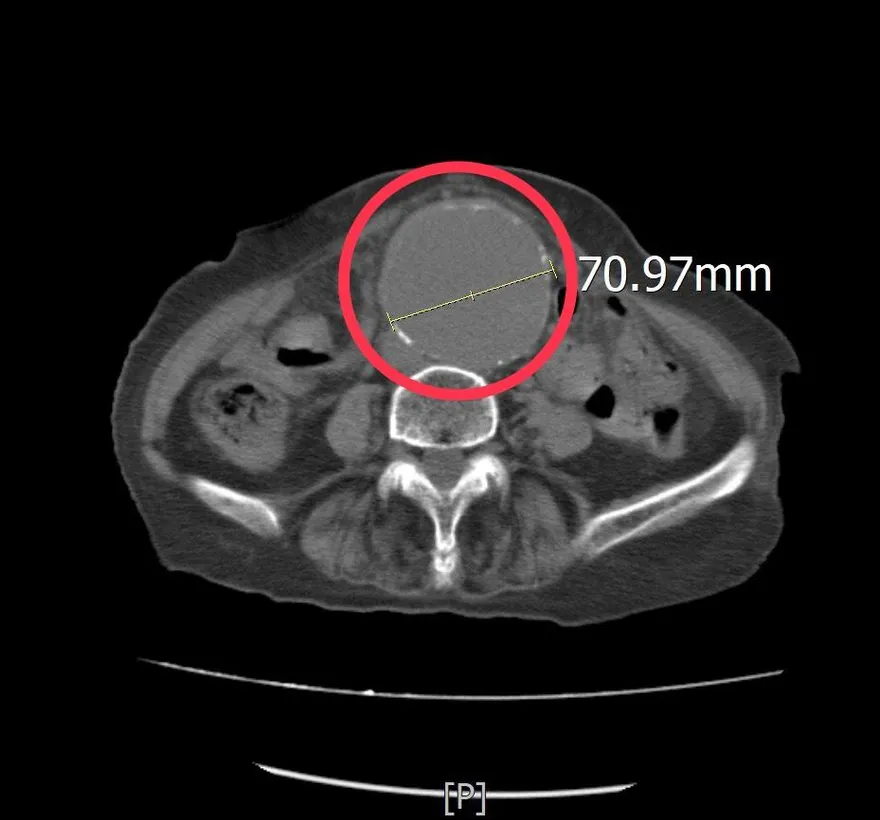

腳痠一週以為肌肉疲勞!8旬婦急診查出7公分腹主動脈瘤